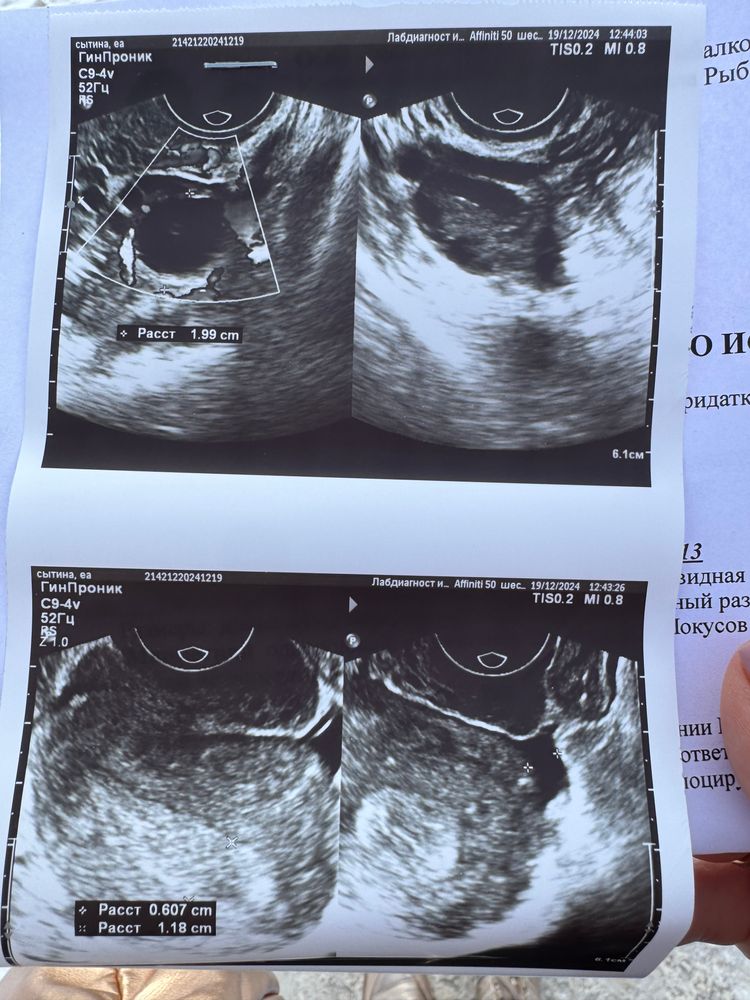

Судя по то, что есть желтое тело и наличие жидкости в позадиматочном пространстве, то О. уже случилась. По всей видимости вчера или прошедшей ночью. Я бы приставала к мужу именно сегодня. Завтра может быть поздно потому что с момента О. (выхода яйцеклетки из фолликула) она живет 12-48 часов, но в среднем 24ч

Если вчера была О., то сегодня 1 ДПО.